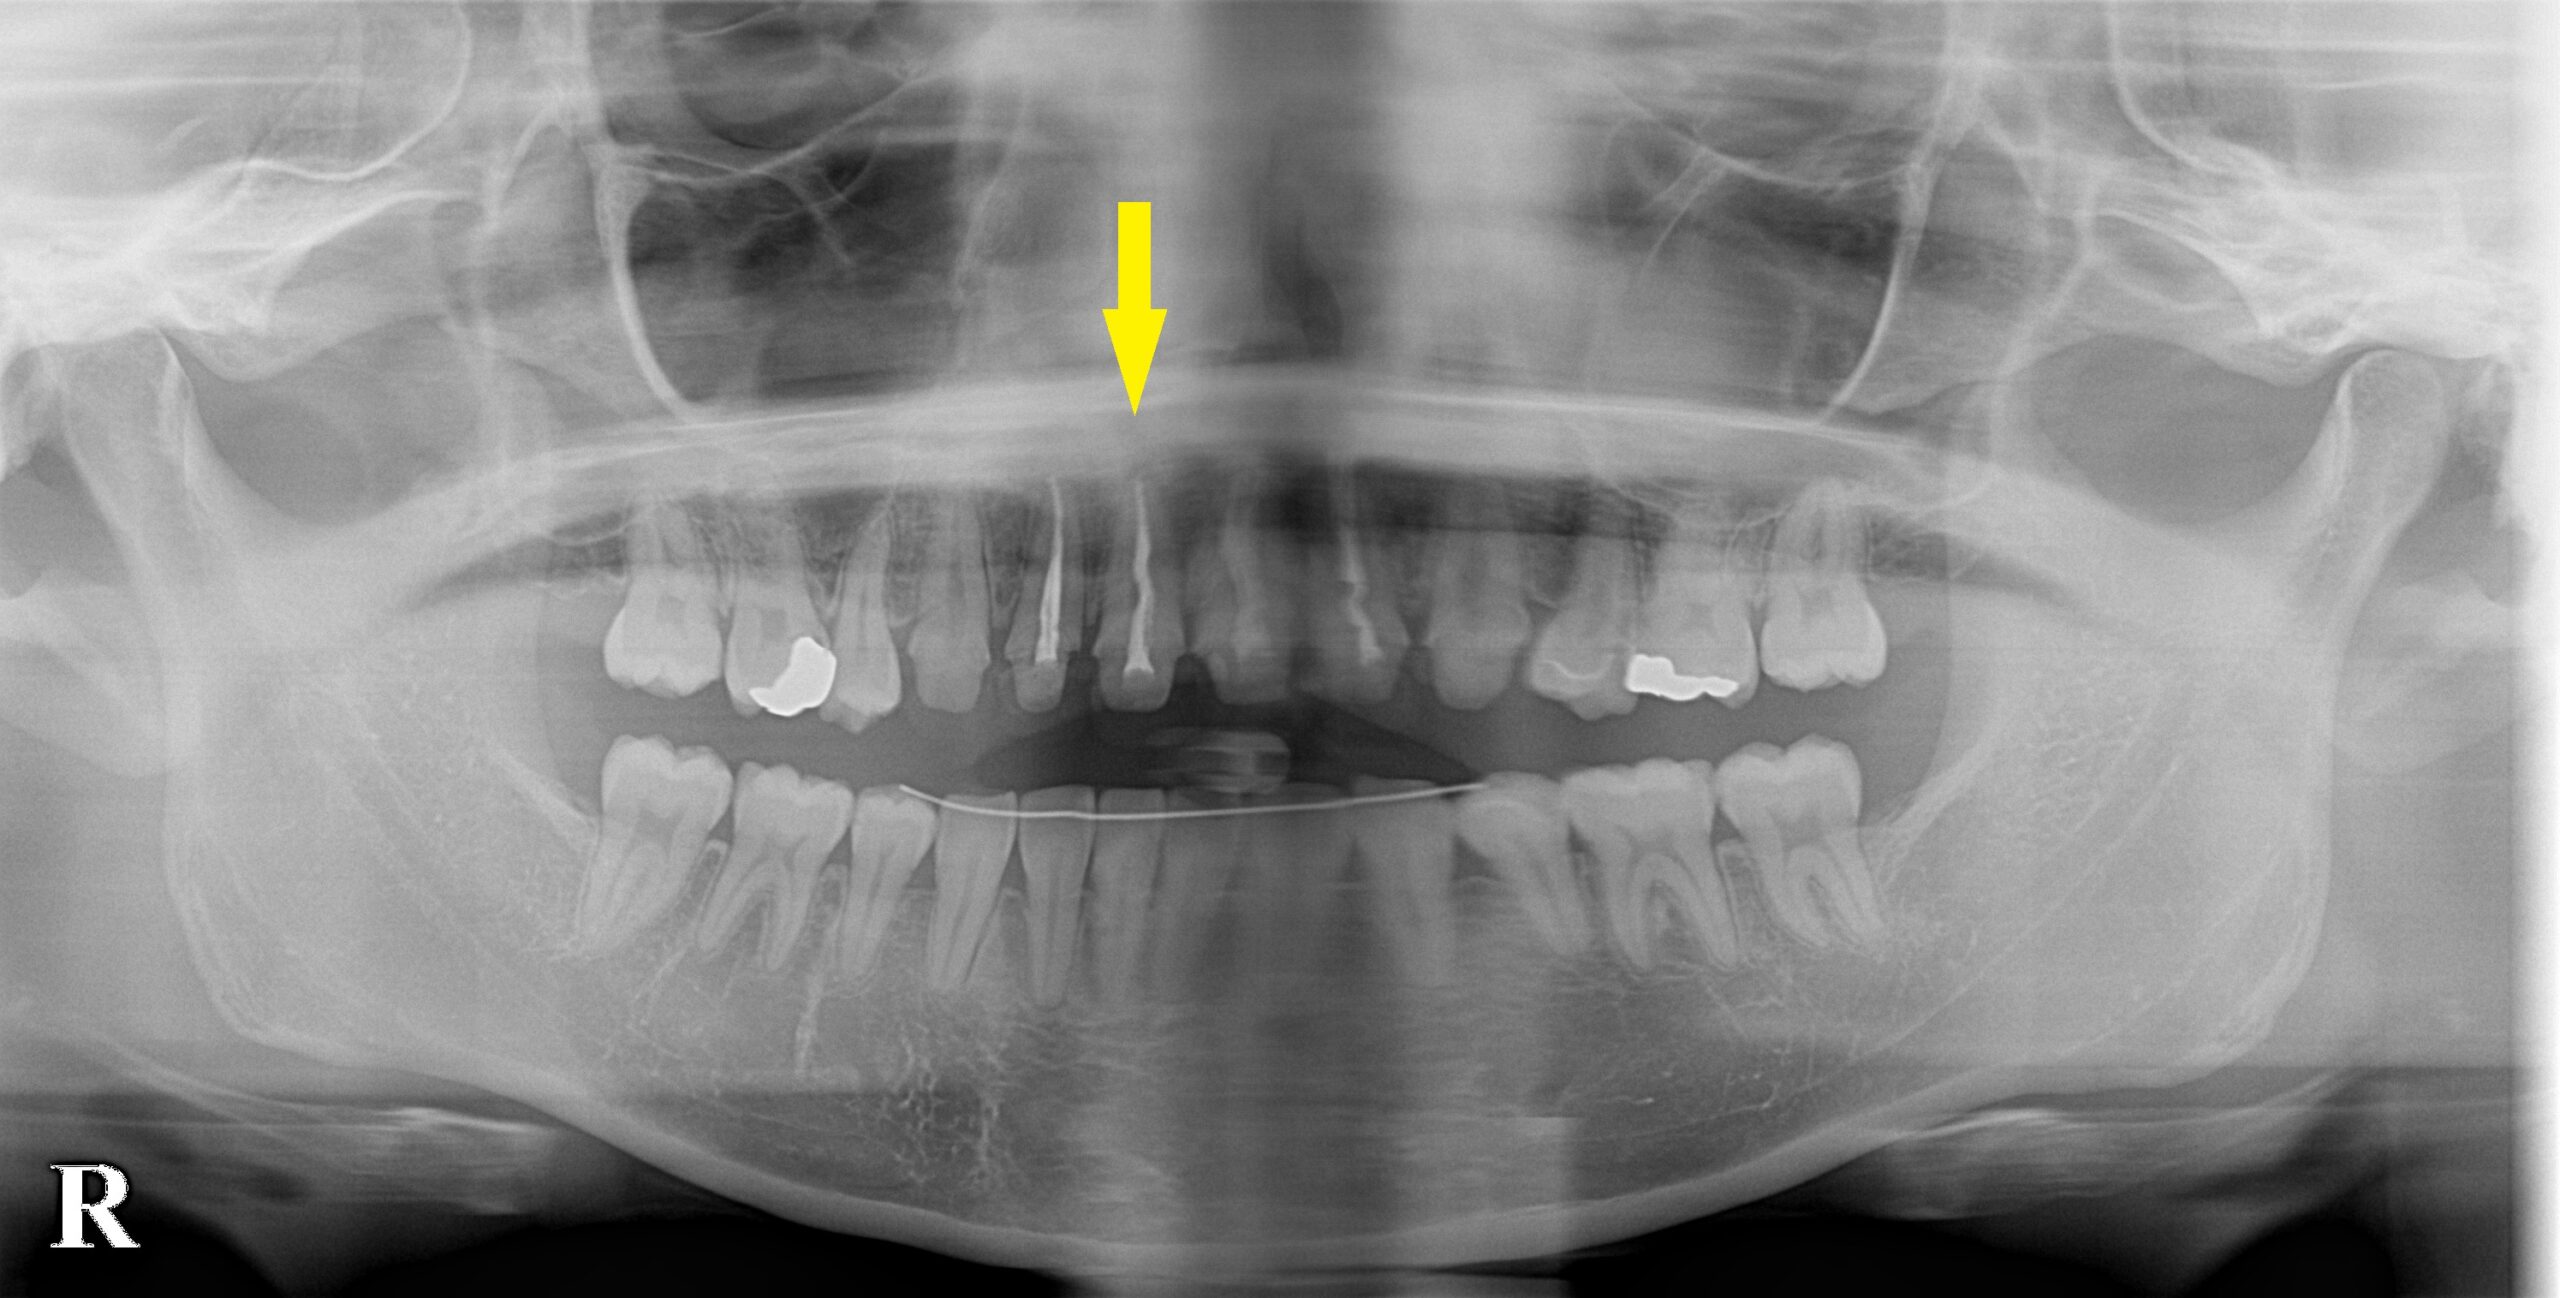

患者様は名古屋在住の30代女性。

右上顎の前歯の歯肉が何度も腫れてきて、その度に歯肉切開や投薬、歯根治療を繰り返しされてきたそうです。

それでも症状は収まらないので、もう抜歯してブリッジかインプラントにしなければならないと言われたそうです。

CTで見ると、この歯の唇側の骨が吸収されて、膿も出ていると思われました(下の写真下段左)。

おそらく、歯根の側方に亀裂か、穴が空いていて、歯根の治療では細菌が完全に排除できないためではないかと考えられました。

抜歯して、インプラントが良いのではないかと説明させていただき、了承していただけました。

まずは抜歯し、歯肉の治癒を2か月待って、インプラント埋入と同時に、骨のなくなった唇側に人工骨を補填して、骨造成を行いました(下の写真下段右)。

上顎前歯の骨造成症例

今週のインプラント症例